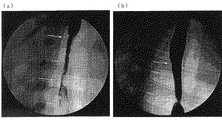

図2に、術後2週間後における、ステントを適用した場合(a)及びステントを適用しなかった場合(b)についての術部の状態を撮影した内視鏡写真を、また、図3に、術後2週間後における、ステントを適用した場合(a)及びステントを適用しなかった場合(b)についての術部を解剖した状態を撮影した写真を示した。なお、図2(a)には、ステント端を固定した内視鏡クリップも写っている。

図2、3より、ステントを適用した場合には、適用しなかった場合に比べて狭窄が軽度であり、早期の創傷治癒が認められた。Endoscopic mucosal resection was performed on the thoracic esophagus of the pig. After inserting the stent obtained in the tubular sheath into the position where the mucosa of the esophagus was excised, the sheath was removed and the stent was released to the affected area. As a comparison object, after performing endoscopic mucosal resection for the entire circumference, the stent was not applied.

FIG. 2 shows an endoscopic photograph of the state of the surgical site when the stent is applied (a) and when the stent is not applied (b) two weeks after the operation, and FIG. The photograph which image | photographed the state which dissected the operation part about the case where a stent is applied (a) and the case where a stent is not applied (b) in two weeks after an operation was shown. FIG. 2A also shows an endoscope clip with the stent end fixed.

2 and 3, when the stent was applied, stenosis was milder than when the stent was not applied, and early wound healing was observed.